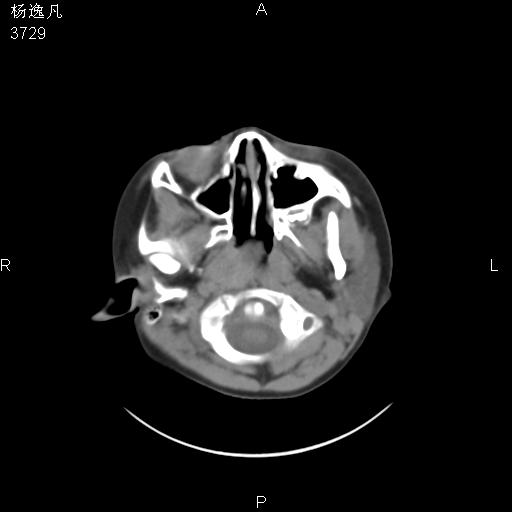

男性,5岁,面部受外伤,余无特殊

薄层

1、右面部及颞部软组织肿胀。

2、腺样体肥大。

头颅ct平扫未见明确外伤性征象,右侧面部及颞部软组织肿胀,后鼻腔软组织影增大,增厚,鼻咽顶部变窄,考虑鼻咽腺样体增值肥厚。